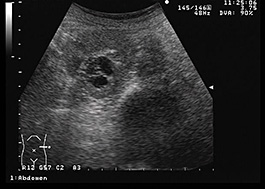

転移性腎細胞癌

がんは、免疫系の一部であるリンパ節(首、脇の下、鼠径部などの領域にある小さな腺)に転移することがあります。

リンパ節は通常、ウイルス、細菌、その他の外来侵入者を捕捉するのに役立ちます。病気やがんにかかっていると腫れることがあります。